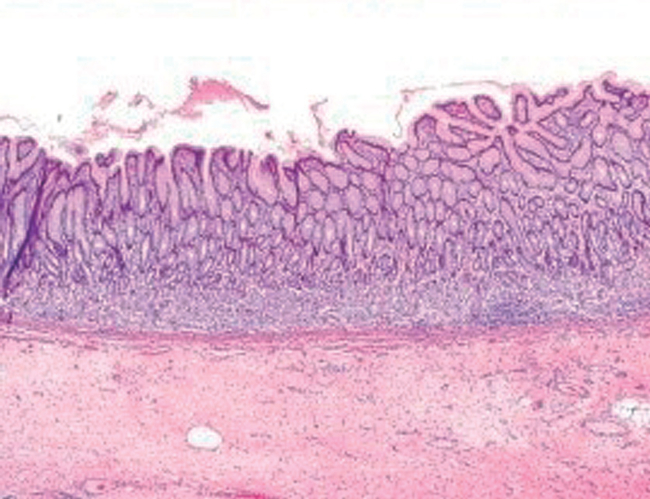

El antro gástrico está constituído por glándulas mucosas redondeadas y con muy poca lámina propia visible entre ambas. El área foveolar representa un 1/3 del espesor total de la mucosa.

El epitelio de superficie es cilíndrico con núcleos ovales y basales y rico en mucinas neutras (Figura 1).

La lámina propia presenta tejido colágeno laxo y escaso infiltrado inflamatorio que no supera 5 linfocitos por campo de gran aumento.